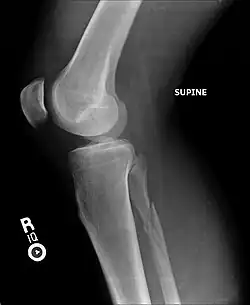

X-ray, CT, or MRI scans can be used to diagnose the extent of the Maisonneuve fracture's damage and determine whether it is a simple or comminution fracture.[8] During diagnosis, a supination-external rotation pattern of injury may also be concluded if there is an isolated fracture of the posterior tubercle of the tibia.[9]